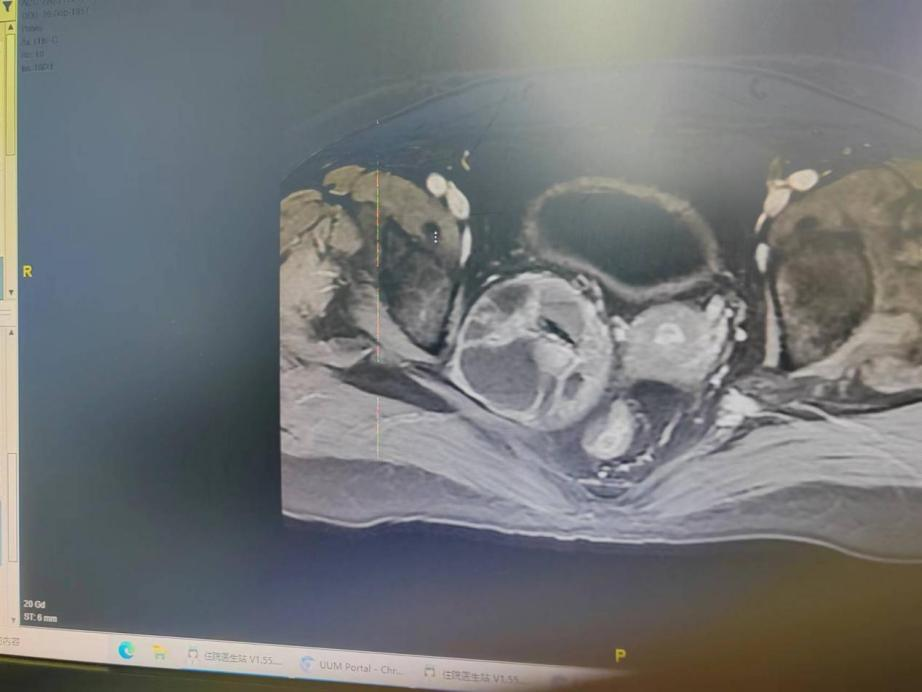

近日与妇瘤科一同完成了一例高难盆腔闭孔区肿瘤手术。手术分为以下步骤:

病理诊断结果:盆腔右侧闭孔神经鞘瘤!

资料照